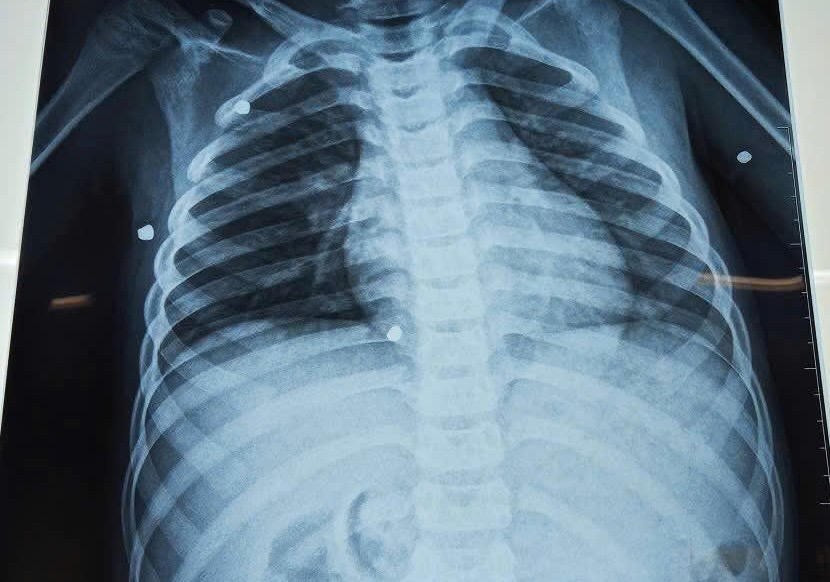

Kết quả chụp X-quang cho thấy có nhiều dị vật cản quang nằm rải rác ở nhiều vị trí trong cơ thể. Ảnh: Trần Tuyền

Qua thăm khám, các bác sĩ phát hiện nhiều vết thương do hỏa khí tại vùng ngực và hai tay. Kết quả chụp X-quang cho thấy có nhiều dị vật cản quang nằm rải rác ở nhiều vị trí trong cơ thể.